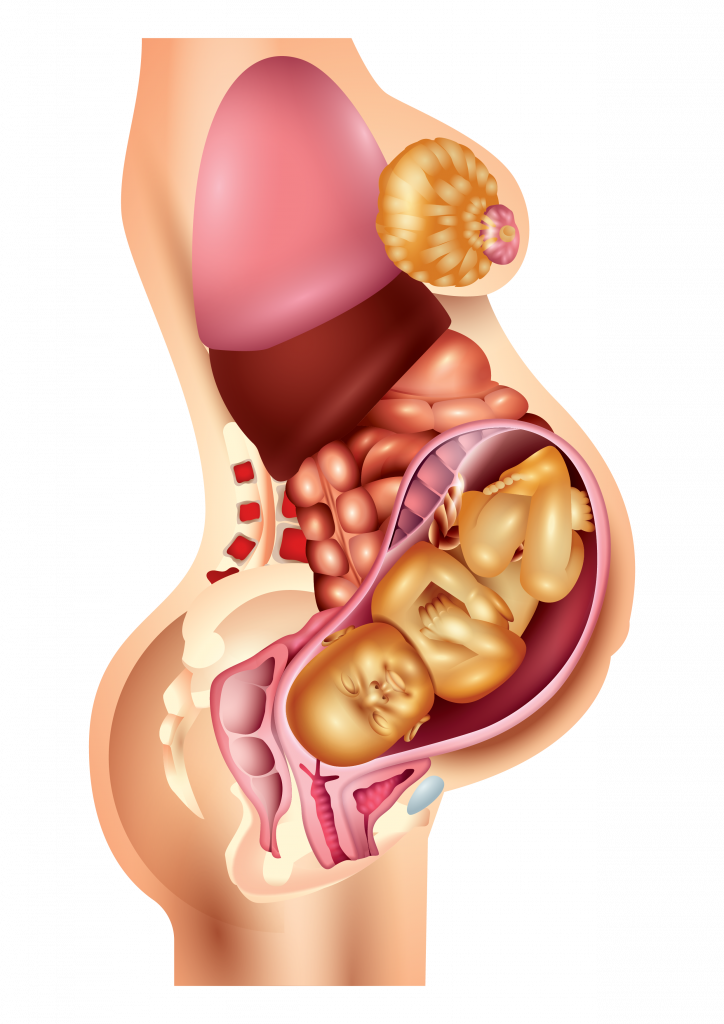

Физиология беременности: строение органов

Раздел: Моменты озарения